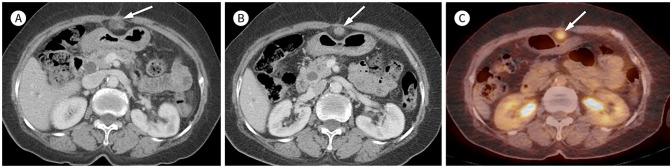

Xanthogranulomatous (XG) inflammatory disease is a rare benign disease involving various organs, including the gallbladder, bile duct, pancreas, spleen, stomach, small bowel, colon, appendix, kidney, adrenal gland, urachus, urinary bladder, retroperitoneum, and female genital organs. The imaging features of XG inflammatory disease are nonspecific, usually presenting as a heterogeneous solid or cystic mass. The disease may also extend to adjacent structures. Due to its aggressive nature, it is occasionally misdiagnosed as a malignant neoplasm. Herein, we review the radiological features and clinical manifestations of XG inflammatory diseases in various organs of the abdomen and pelvis.

黄色肉芽肿性(XG)炎性疾病是一种罕见的良性疾病,可累及包括胆囊、胆管、胰腺、脾脏、胃、小肠、结肠、阑尾、肾脏、肾上腺、脐尿管、膀胱、腹膜后间隙及女性生殖器官在内的多个器官。XG炎性疾病的影像学特征不具有特异性,通常表现为不均匀的实性或囊性肿块。该疾病也可能蔓延至相邻结构。因其具有侵袭性,偶尔会被误诊为恶性肿瘤。在此,我们回顾腹部和盆腔各器官XG炎性疾病的放射学特征及临床表现。